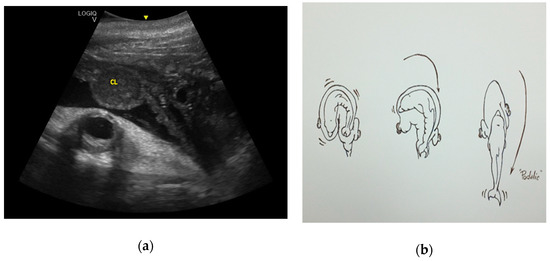

- Deng, X.; Hao, Y.; Serres, A.; Wang, K.; Wang, D. Position at Birth and Possible Effects on Calf Survival in Finless Porpoises (Neophocaena asiaeorientalis). Aquat. Mamm. 2019, 45, 4. [Google Scholar] [CrossRef]

- Gol’din, P.E. Case of cephalic presentation of fetus in a harbor porpoise (Phocoena phocoena), with notes on other aquatic mammals. Vestn. zool. 2011, 45, 33–38. [Google Scholar]

- Essapian, F.K. Observations on Abnormalities of Parturition in Captive Bottle-Nosed Dolphins, Tursiops truncatus, and Concurrent Behavior of Other Porpoises. J. Mammal. 1963, 44, 405–414. [Google Scholar] [CrossRef]

- Hart, P.; Van der Kemp, J.S. Cephalic presentation observed in a white-beaked dolphin, Lagenorhynchus albirostris. Lutra 1999, 41, 21–24. [Google Scholar]